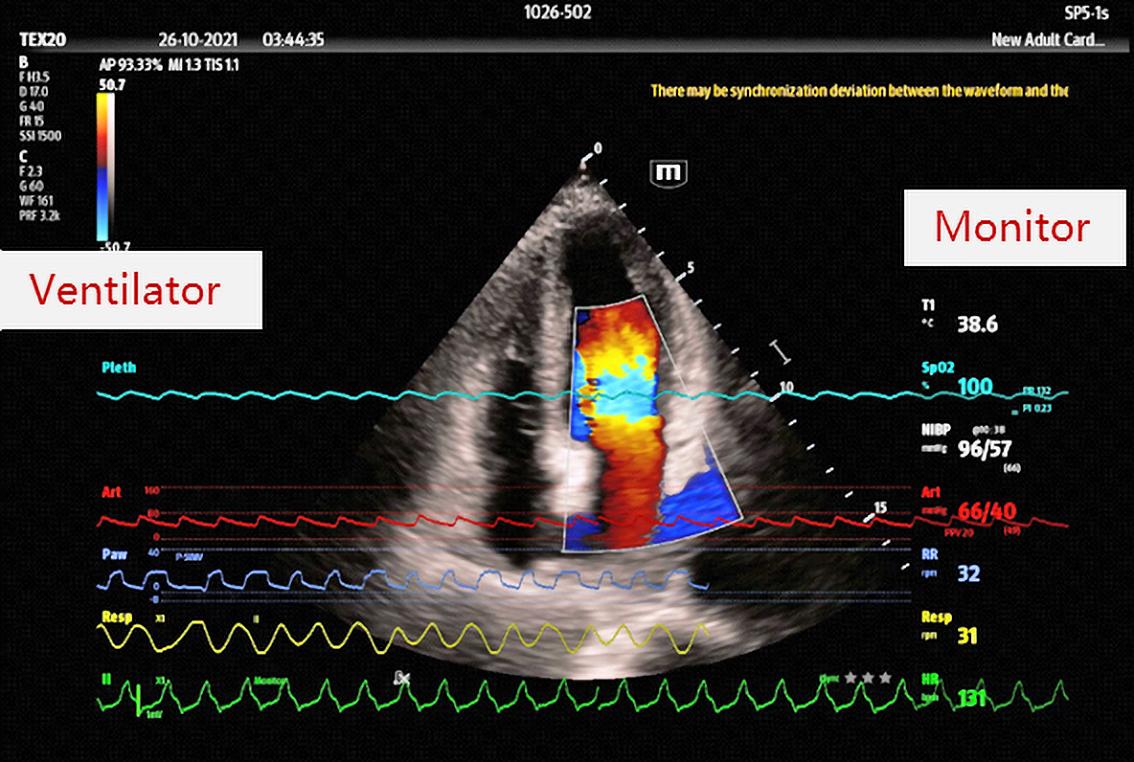

Printre proiectele care m-au bucurat în 2023 și 2024 aș sublinia că am avut plăcerea ca în ianuarie 2024 să fiu profesorul primei generații de medici ATI pentru atestatul de competență în ecocardiografie transtoracică transesofagiană, ecografie pulmonară și vasculară pentru abordul vascular – UPCATI.